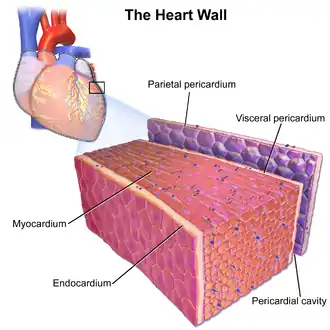

| Constrictive pericarditis is defined by a fibrotic (thickened) pericardium. | |

Constrictive pericarditis is a condition characterized by a thickened, fibrotic pericardium, limiting the heart's ability to function normally.[1] In many cases, the condition continues to be difficult to diagnose and therefore benefits from a good understanding of the underlying cause.[2]

The pathophysiological characteristics of constrictive pericarditis are due to a thickened, fibrotic pericardium that forms a non-compliant shell around the heart. This shell prevents the heart from expanding when blood enters it. As pressure on the heart increases, the stroke volume decreases as a result of a reduction in the diastolic expansion in the chambers. [6] This results in significant respiratory variation in blood flow in the chambers of the heart.[7]